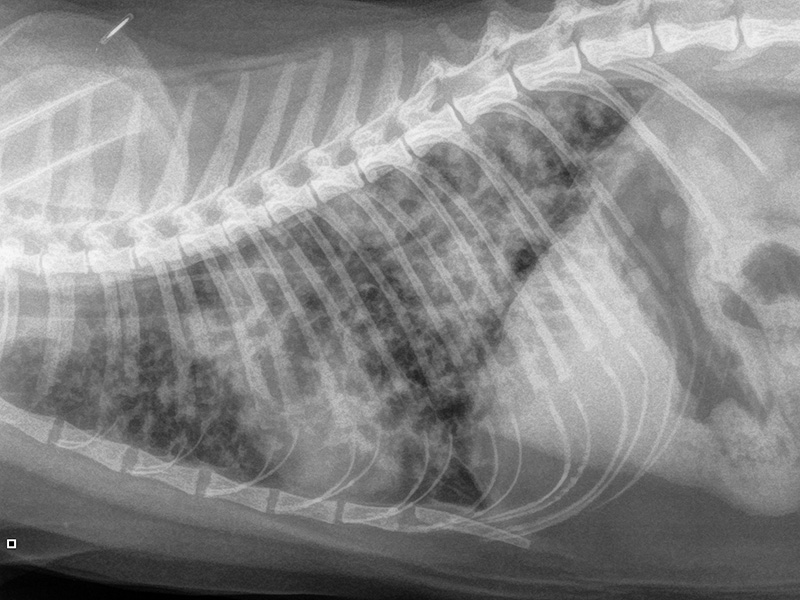

- Imaging: Film reading and more: imaging the thorax does not always have to be frustrating (TBC)

- Medicine 1: Thoracic POCUS for dyspnoeic cats: keep the xray machine turned off? (Sam Taylor)